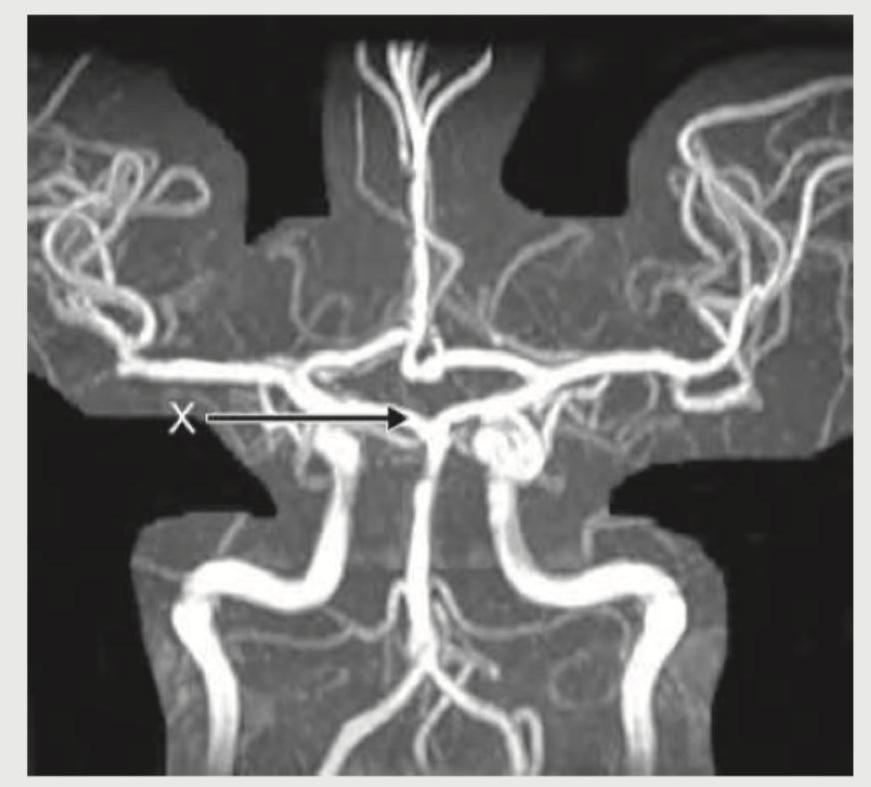

What is the name of the marked blood vessel in the Circle of Willis?

Explanation: ***Posterior communicating artery*** - The image displays the Circle of Willis, and the vessel marked with 'X' is connecting the **internal carotid artery** (which branches into the middle and anterior cerebral arteries) to the **posterior cerebral artery**. - This connecting artery is the **posterior communicating artery**, an essential component of the Circle of Willis, ensuring collateral blood flow to the brain. *Middle cerebral artery* - The **middle cerebral artery** branches off the internal carotid artery and typically extends laterally into the Sylvian fissure, supplying a large part of the lateral cerebral cortex. - The marked vessel is clearly connecting proximal arteries within the Circle of Willis, not extending into the cerebral cortex peripherally. *Internal carotid artery* - The **internal carotid artery** enters the skull and gives rise to several branches, including the middle cerebral artery and the posterior communicating artery. - While it's part of the supply to the Circle of Willis, the 'X' points specifically to the **communicating segment** connecting the anterior and posterior circulations, not the main trunk of the internal carotid. *Posterior cerebral artery* - The **posterior cerebral artery** is formed by the bifurcation of the basilar artery and supplies the occipital lobe and parts of the temporal lobe. - The marked vessel is connecting to the posterior cerebral artery, but it is not the posterior cerebral artery itself; rather, it is the vessel **communicating** with it from the anterior circulation.